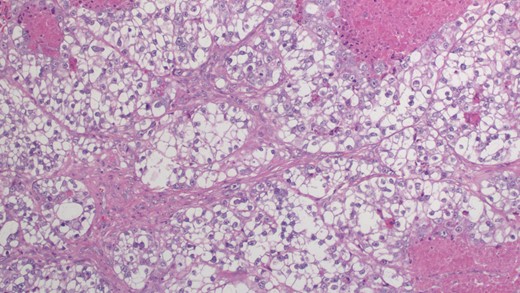

In our patient, the breast core biopsy showed multiple tiny foci of papillary proliferation with pseudo-lactational changes. However, the open biopsy showed poorly differentiated invasive ductal carcinoma with clear cell changes (Fig. 1). Ductal carcinoma in situ displays a papillary pattern with focal cystic hypersecretory (pseudo-lactating) features (Fig. 2). Microscopic examination showed that the tumor cells contained abundant fine glycogen granules in their clear cytoplasm, which were stained by a periodic acid-schiff (PAS) stain, but not stained by a diastase-PAS stain. There were features of poorly differentiated carcinoma with a prominent micropapillary growth pattern. Extensive ductal carcinoma in situ with solid, micropapillary, flat and cribriform types with an intermediate-to-high nuclear grade with necrosis was also noted. Invasive and in situ carcinomas both show clear cell and cystic hypersecretory changes. The breast core biopsy specimen showed atypical ductal hyperplasia with clear cell changes.

Microscopic examination reveals tumor cells with ample clear cytoplasm, distinct cell borders and pleomorphic nuclear features (×20).